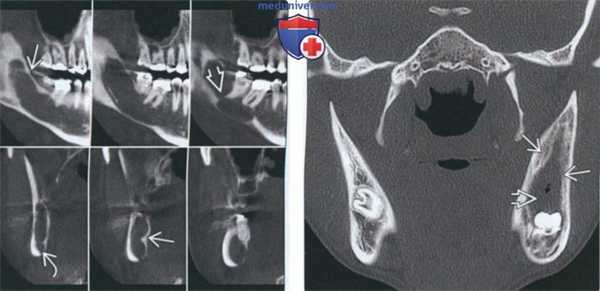

(Слева) На панорамной реформатированной КЛКТ определяются перикоронарные просветления вокруг второго и третьего моляров нижней челюсти справа, являющиеся двумя отдельными патологическими очагами: ОКК, связанной с третьим моляром, и зубной кистой, связанной со вторым моляром.

(Справа) На аксиальной КЛКТ у этого же пациента определяется смещение второго моляра с дистально ориентированной коронкой в щечную сторону. Зубная киста прикрепляется к ЦЭС. (Слева) На корональной КТ в костном окне определяется огромная зубная киста, связанная с третьим моляром верхней челюсти слева. Значительное смещение связанного зуба, особенно в верхнечелюстную пазуху, - типичный признак зубных кист. Обратите внимание на отсутствие латеральной стенки пазухи.

(Справа) На MPT (Т1 ВИ) у этого же пациента визуализируется зуб в виде участка выпадения сигнала. Латеральная стенка пазухи сохранена, однако на этом срезе определяется распроаранение патологического очага вдоль неба. (Слева) На аксиальной КТ в костном окне визуализируется вторично инфицированная зубная киаа, связанная с третьим моляром нижней челюсти слева. Обратите внимание на периостальную реакцию со стороны щечной и язычной кортикальной пластинки.

(Справа) На корональной КТ в костном окне у этот же пациента определяется нарушение целостности щечной кортикальной пластинки, обусловленное синусным трактом, на фоне периостальной реакции с щечной стороны. Обратите внимание на отсутствие отграничивающей кортикальной пластинки, что позволяет предположить инфекцию или другой патологический процесс. Склероз окружающей кости означает воспалительный ответ.